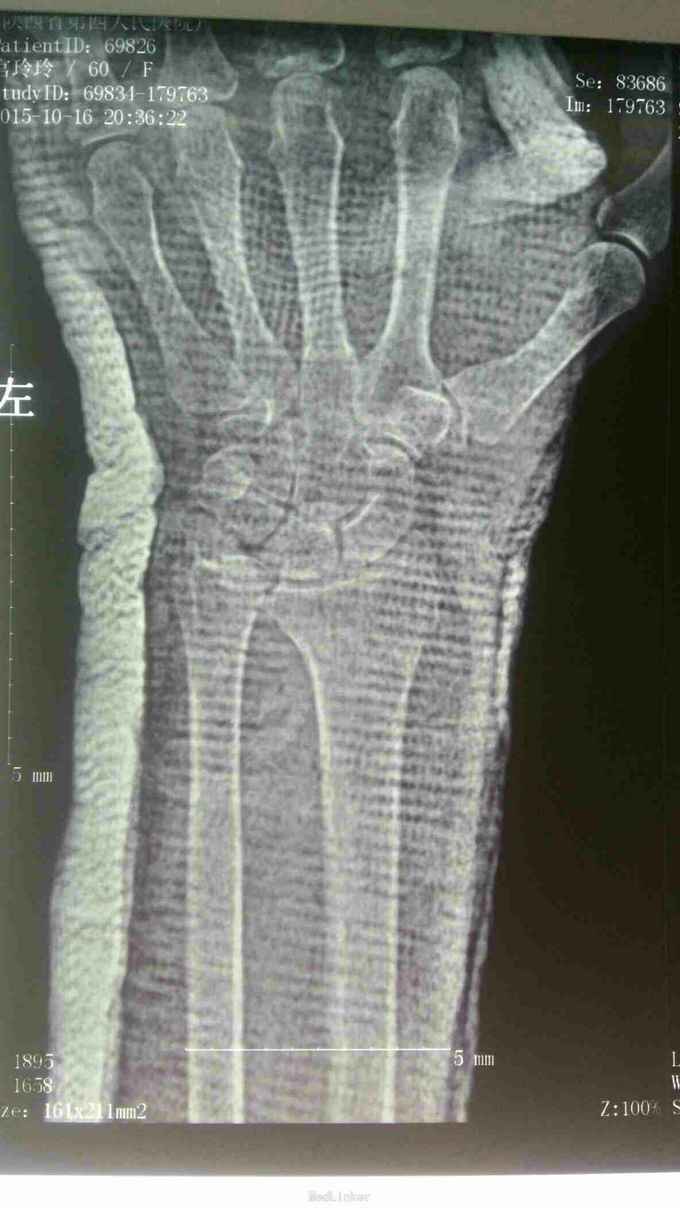

主诉:患者女性,60岁,摔倒致左腕肿痛、活动障碍2小时。 病史:2小时前,坐电动车摔倒,左手着地,感左腕疼痛,肿胀、活动受限。

查体:左腕肿胀明显,腕关节屈伸活动受限,桡动脉搏动存在,各指活动部分受限。 辅查:X线片示左桡骨远端骨折,尺骨小头脱位

诊断:左桡骨远端骨折(Smith骨折) 左尺骨小头脱位 治疗:局部浸润麻醉下行骨折脱位手法复位,然后背伸位行腕部掌侧石膏托固定。再拍片复查,尺骨脱位已复位,但桡骨远端向掌侧移位没有纠正。